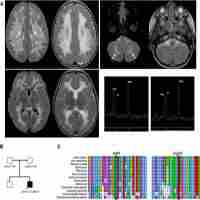

| Abstract | Background Neurodegeneration due to cerebral folate transport deficiency is a rare autosomal recessive disorder caused by biallelic pathogenic variants in FOLR1. Onset typically occurs in late infancy and is characterized by psychomotor regression, epilepsy, and a hypomyelinating leukodystrophy on magnetic resonance imaging. If left untreated, progressive neurodegeneration occurs. However, early treatment with folinic acid has been shown to stabilize or reverse neurological features. Approximately thirty patients have been described worldwide. Here, we report the first two cases with genetically proven cerebral folate transport deficiency from South-Eastern Europe, describe the effect of oral folinic acid therapy on clinical and neuroradiological features and review the literature. Results Two siblings presented in childhood with clinical and radiological findings consistent with a hypomyelinating leukodystrophy. Exome sequencing revealed a novel homozygous pathogenic variant in FOLR1 (c.465_466delinsTG; p.W156G), confirming the diagnosis of neurodegeneration due to cerebral folate transport deficiency. Folinic acid treatment was promptly initiated in both patients. The younger sibling was treated early in disease course at 2 years of age, and demonstrated complete recovery in clinical and MRI features. The older sibling, who was 8 years of age at the time of diagnosis and treatment, demonstrated partial but substantial improvements. Conclusion We present the first account in the literature that early treatment initiation with oral folinic acid alone can result in complete neurological recovery of both clinical and radiological abnormalities in neurodegeneration due to cerebral folate deficiency. Moreover, through the report of these patients along with review of the literature, we provide information about the natural history of the disease with comparison of treatment effects at different stages of disease progression. This report also reinforces the importance of universal access to genetic testing to ensure prompt diagnoses for treatable disorders. |